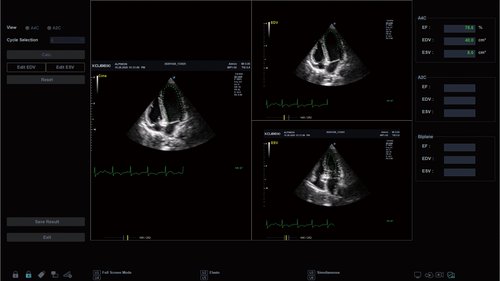

Ein wesentlicher Fokus liegt beim X-CUBE 70 auf der Vereinfachung und Anpassung der Bedienung. Ein erweitertes Spektrum an automatisierten Messungen und individuell programmierbare Workflows ermöglichen ein diagnosefokussiertes Arbeiten in jeder Situation.

eXpanded Capability

Das X-CUBE 70 bietet modernste Technologien für eine objektive und akkurate Diagnose. Intelligente klinische Module heben das System auf ein neues diagnostisches Niveau. Es erweitert Ihre Fähigkeiten und die Bandbreite Ihrer Möglichkeiten. Dazu gehören Module wie MicroView, point Shear Wave Elastographie (pSWE), oder auch die Kontrastmittelsonographie.

eXpanded Care

Individuell programmierbare Workflows ermöglichen Ihnen einen optimalen Arbeitsfluss, damit der Fokus auf die Diagnose und den Patienten gerichtet wird. Der X+ Assistant ist ihr persönlicher Assistent.